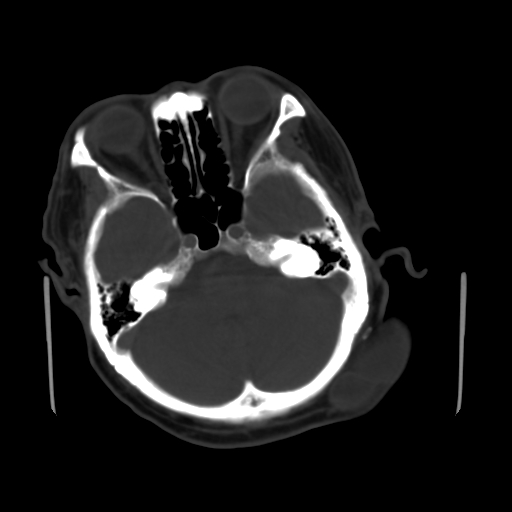

标题: CT25147:男,62岁,右侧肢体活动障碍不灵活三天。 [打印本页]

男,62岁,右侧肢体活动障碍不灵活三天,左侧头皮肿物十余年(ct值8hu)。

多发腔梗!皮下脂肪瘤!

1)多发性腔隙性脑梗塞。2)脑白质病。3)脑萎缩。4)左侧枕顶部头皮下皮样囊肿,不排除脂肪瘤。